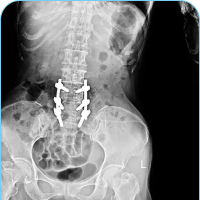

The Spinal Column is also called the vertebral column. The bones in the spine are called vertebrae (ver-ta-bray). The column starts at the base of the skull and continues to the pelvis. Alternate layers of bone (vertebrae) and cartilage (car-til-ledge, the intervertebral discs) stack vertically one on top of the other in the spinal column. The lattice-like structure of the cancellous bone (cancel-lus, the spongy interior) in a vertebra absorbs external pressure. The human spine has natural curvatures. When you look at a back from behind, the spine should be straight and centered over the pelvis.

However, when you look at the spine from the side, the curves are designed to maintain balance as the spine is behind organs in the chest and abdomen. The spine has two alternating curves to create an “S” like shape. In the neck and low back there is normally an inward curvature or sway back known as lordosis. In the thoracic spine and sacrum there is an outward curvature known has kyphosis or hunchback. These curves normally balance out each other so that when the patient stands they are well balanced with their head straight above their hips when viewed from the side. Standing in this position minimizes the effect of gravity and allows the patient to stand with the best posture and use the least energy when moving or walking. There are seven cervical (C) vertebrae, twelve thoracic (T) vertebrae, and typically five lumbar (L) vertebrae.

There are usually five lumbar vertebrae, named L1-L5, designed for weight bearing loads and movement. In some people, they may have developed four or six lumbar vertebrae. In some cases one of the bones of the sacrum, the base of the spine, forms as a vertebra instead of the sacrum. This is called a transitional (or sixth) vertebra and is simply a bony anomaly.

The lumbar spine is shaped like the cervical spine; it is lordotic like a backwards “C”. The two lordotic curves in the neck and low back are balanced by the thoracic kyphotic “C” curve so the spine’s center of gravity is overall balanced in an “S” shape. The vertebrae in the lumbar spine are the largest of the entire spine, designed to hold increasing forces of weight. The lumbar spinal canal is also the largest, allowing for more space for the nerves.

SACRUM AND COCCYX

The sacrum is made of five fused vertebrae that form a single bone. The sacrum is shaped like an inverted triangle with the base at the top. It acts as a wedge between the two iliac pelvic bones. On both sides of the pelvis, the sacrum articulates with the ilium through the sacroiliac joints. The coccyx is formed by the fusion of four to five rudimentary vertebrae, commonly referred to as the tailbone.